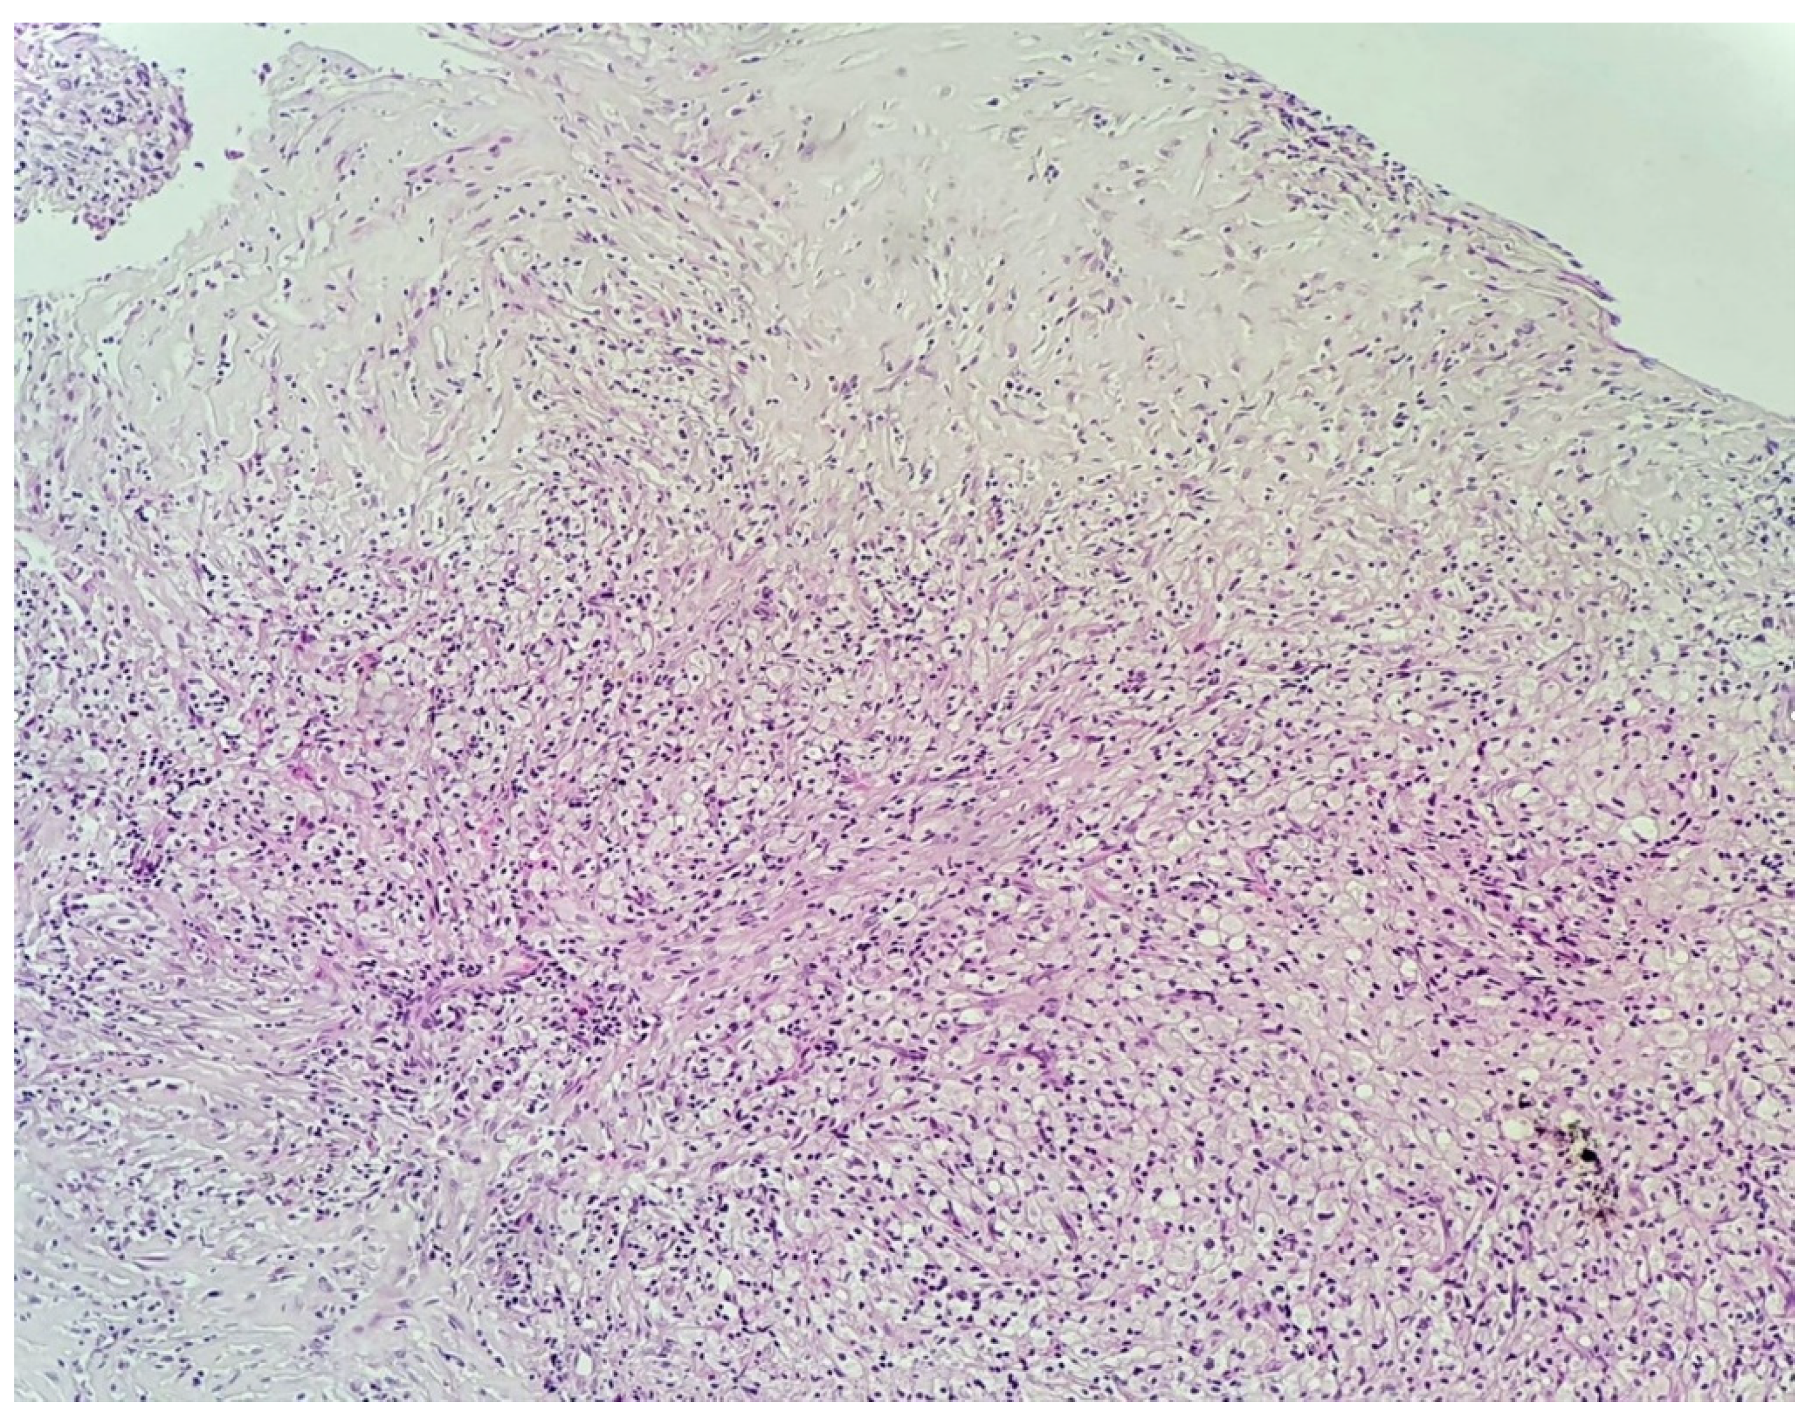

3.2. Histopathological Examination of the Specimen